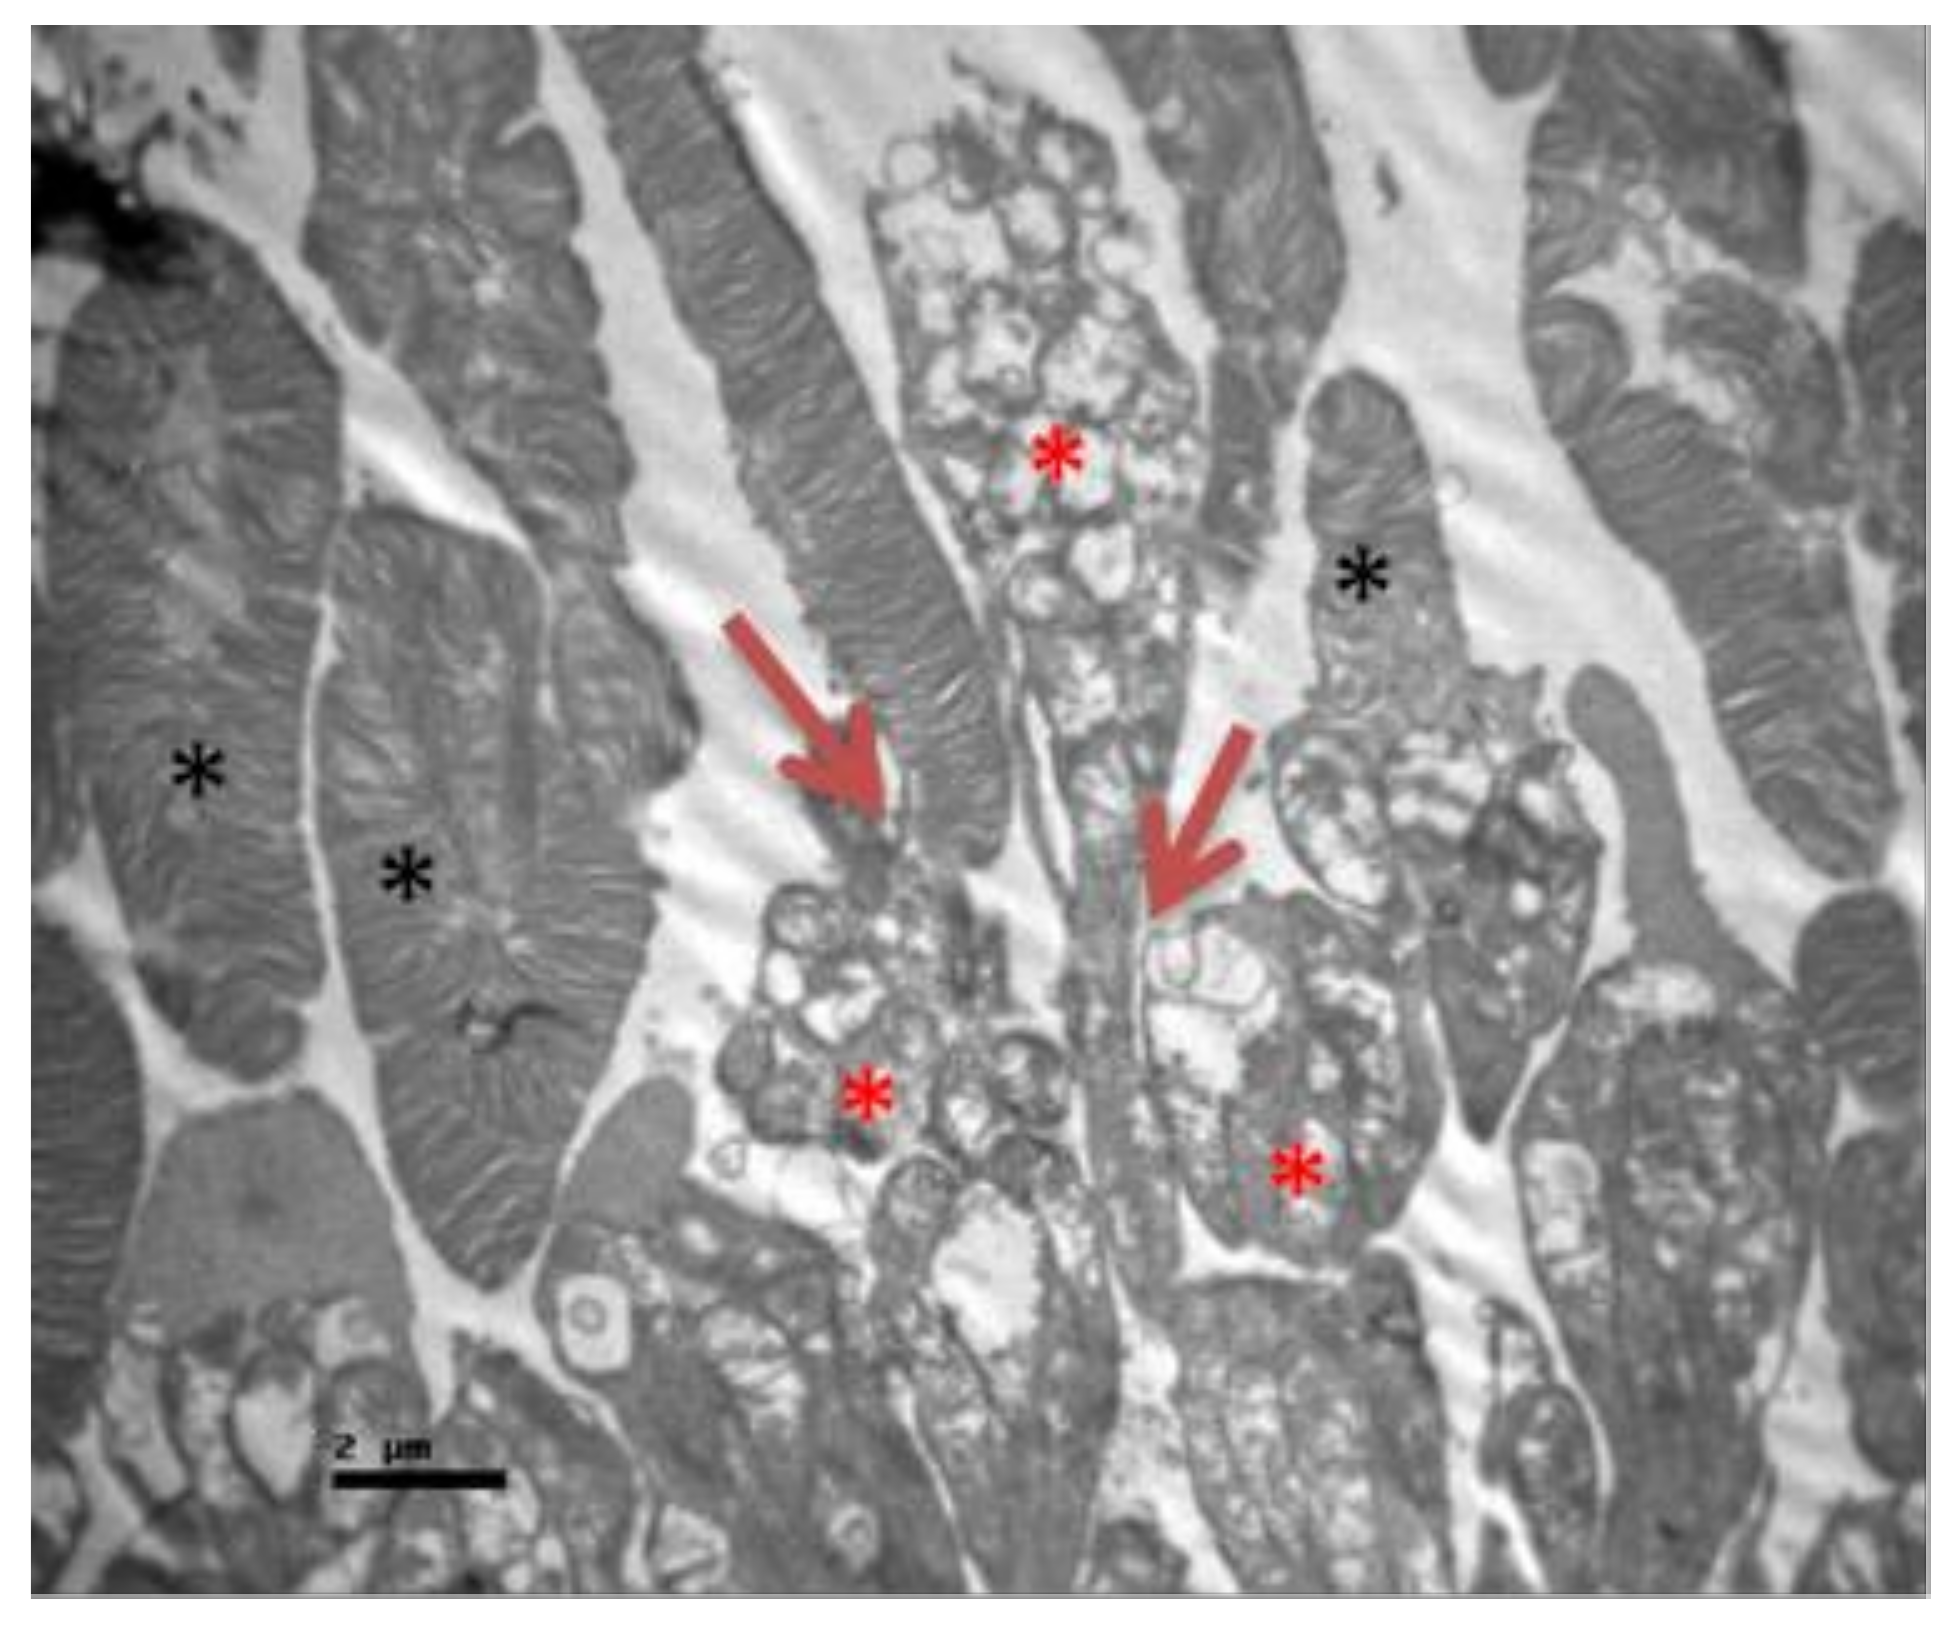

2.2. Group V

2.3. Group M